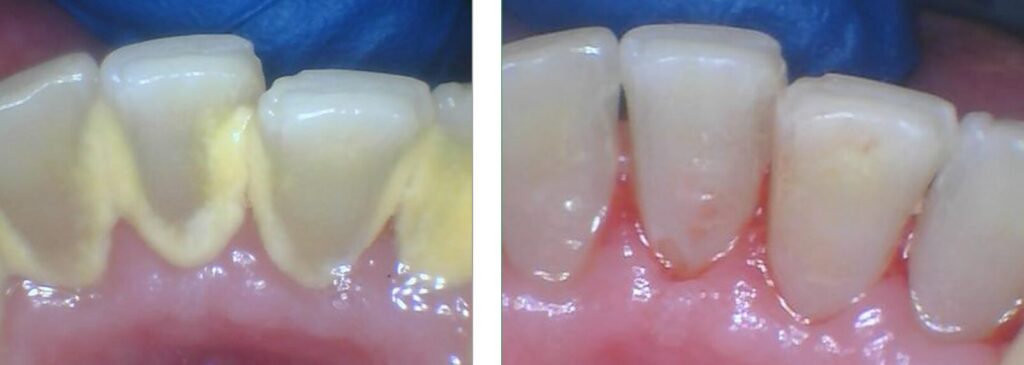

(In the left photo, you can clearly see the yellow dental calculus (tartar) buildup along the gum line. The photo on the right shows the immediate difference after a professional cleaning. At Finesse Dentistry in Boston, we always provide ‘before and after’ pictures so our patients can see the healthy results for themselves.)